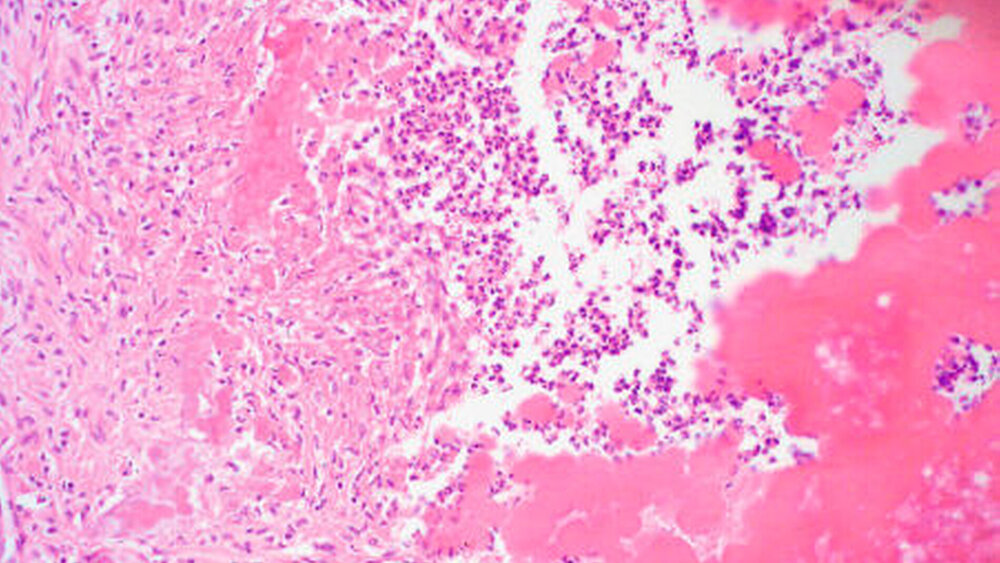

Nach antibiotischer Vorbehandlung wurden die Zähne 74 und 75 extrahiert, das zystische, entzündlich veränderte Gewebe der Region wurde entfernt (Abbildung 4).

Die histopathologische Aufbereitung ergab das Vorliegen einer radikulären Zyste, bei Zahnresten mit nekrotischer Pulpitis und Parodontitis und dem Vorliegen eines ausgeprägten Bakterienrasens.